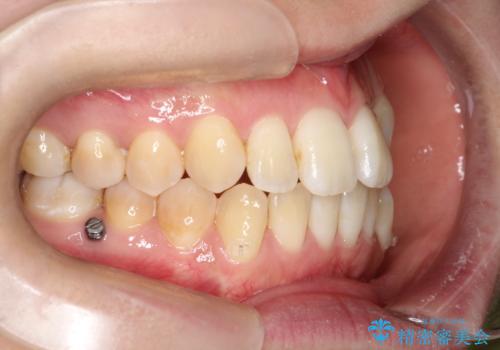

- 前歯のガタガタと、かみ合わせを改善したいとのことで来院されました。

下顎の歯が、上顎の歯に対して前方に位置していたので、下顎の歯を後方に移動させるのと、歯と歯の間を削りスペースを作り、歯を並べる計画としました。

お仕事の関係で使用時間が制限されるときもあり、治療期間が予想より少し長くなりましたが、装置をつけずに治療を終えることができました。